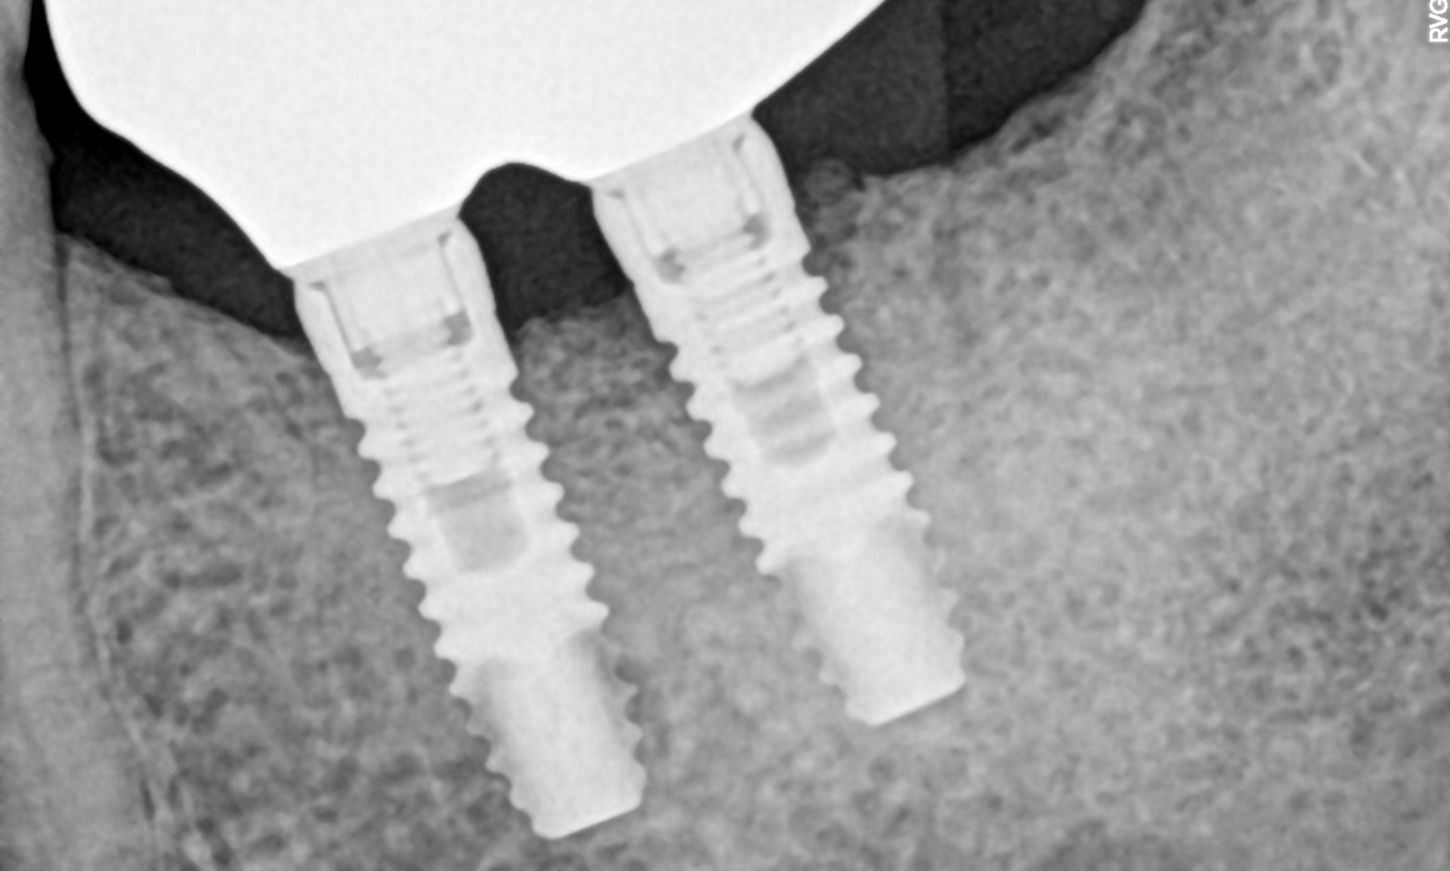

The radiographic examination revealed both horizontal and vertical bone loss around the implants, particularly around implant #37 (Fig. 1).

Fig. 1